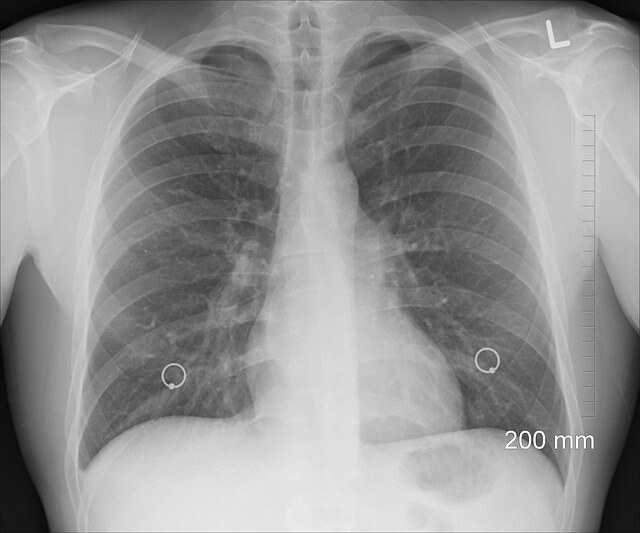

증상이 없더라도 평소에 건강한 습관을 들이면 가슴 통증을 예방하고 전반적인 심폐 건강까지 챙길 수 있습니다. 예방은 언제나 치료보다 현명하고 빠른 길입니다.

- 정기적인 건강검진 받기 (혈압, 심전도, 위내시경 등)